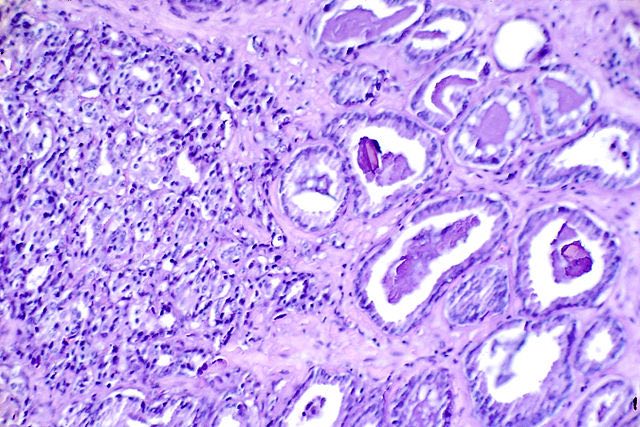

Prostate cancer can be particularly aggressive, especially in patients with certain genetic mutations. Among patients diagnosed with advanced stages of the disease, nearly one in four have alterations in critical DNA repair genes like BRCA1 and BRCA2. For these men, standard hormone treatments such as abiraterone acetate and prednisone often fall short, leading to rapidly worsening symptoms.